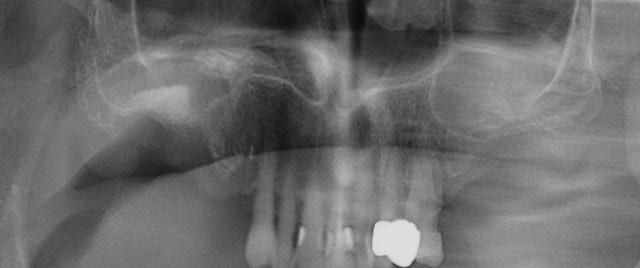

bridge de fou (33-37) qui est tombé il y a une semaine.

si possible 3 implants et le patient est ok pour expansion, reste plus qu'à voir pour le planing...

C'est pas le bridge qui est fou...

c'est les 12 endos au maxillaire !

WOW, jamais vu tant d'endo sur une arcade en 17 ans !

tu as quoi comme hauteur en 34/35/36 par rapport au V3?

j'ai la flemme de mesurer sur l'ecran

j'ai pris les mesures, ça va etre "sportif" V3 "present", os D1, pas de hauteur je prendrais un cognac apres le kirr au petit dej.